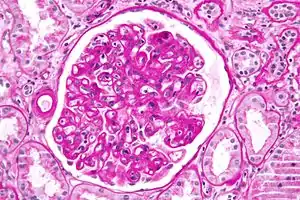

Chronic rejection

Micrograph showing a glomerulus with changes characteristic of a transplant glomerulopathy. Transplant glomerulopathy is considered a form of chronic antibody-mediated rejection. PAS stain.

Chronic rejection is an insidious form of rejection that leads to graft destruction over the course of months, but most often years after tissue transplantation.[12] The mechanism for chronic rejection is yet to be fully understood, but it is known that prior acute rejection episodes are the main clinical predictor for the development of chronic rejection.[6] In particular, the incidence increases following severe or persistent acute rejection, whereas acute rejection episodes with return to function back to baseline do not have major effects on graft survival.[20][21] Chronic rejection is generally thought of as being related to either vascular damage or parenchymal damage with subsequent fibrosis.[22] While it is unknown the exact contribution of the immune system in these processes, the indirect pathway of allorecognition and the associated antibody formation seems to be especially involved.[6]